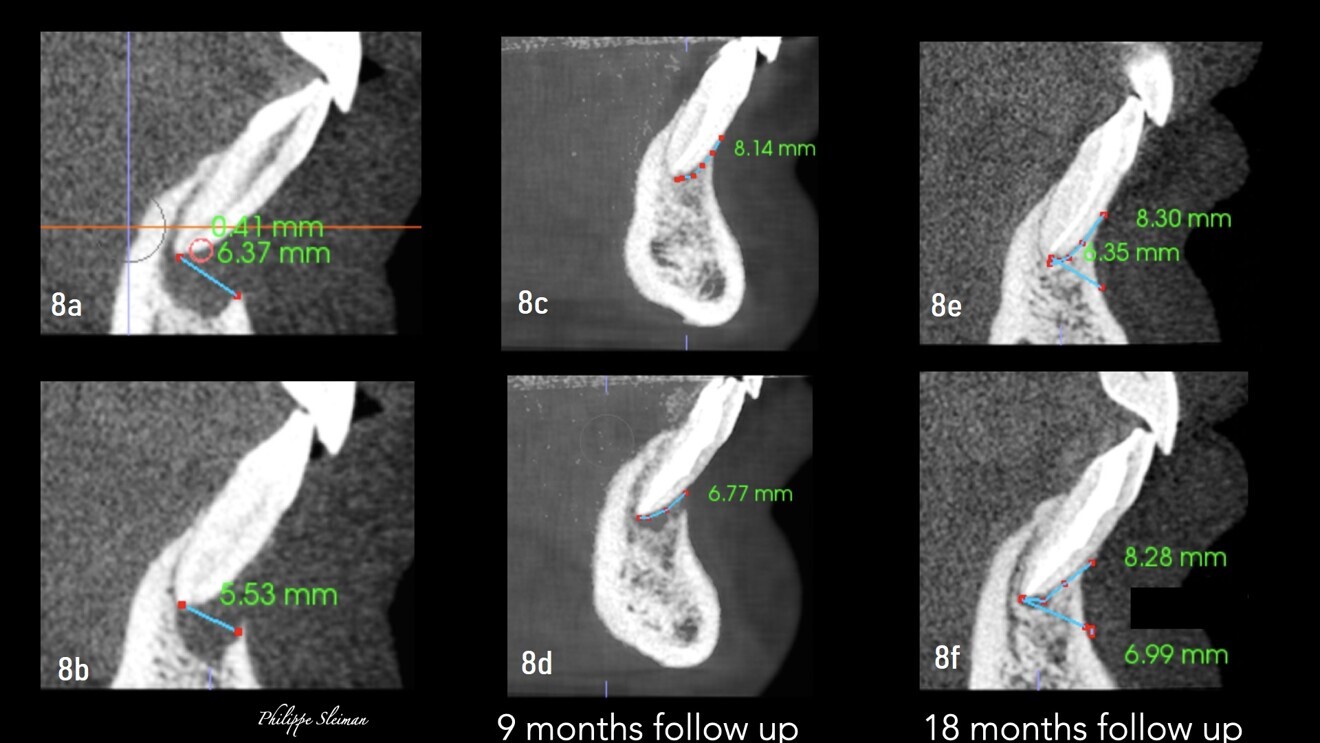

Zero apicectomy, the art of combining root canal treatment and microsurgery to preserve tooth integrity and no longer removing the apex, has been proved a very successful technique not only in preserving the tooth structure but also in recreating a new periodontal ligament where the bone can grow vertically—an idea that was impossible before—in order to save the natural teeth, a new approach in endodontic microsurgery. In a trauma case in which there was an absence of cortical bone and apical bone around the mandibular central incisors and a very deep pocket reaching the apical area, a zero apicectomy and a root canal treatment were done, and 18 months later, against all odds, the bone had grown vertically, covering the buccal part of the root almost completely, and the apical bone was completely restored (Fig. 8).

Figs. 8a–f: Absence of cortical bone and apical bone around both central incisors (a & b). Nine-month follow-up radiographs (c & d). Eighteen-month follow-up radiographs (e & f).